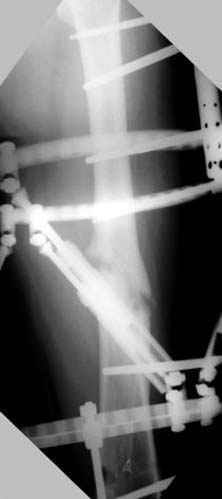

пластическая модель; и коррекция бедра аппаратом Илизарова.

Имею другие снимки тоже, получится как отчет о моей работе.

Узкий к-м канал - тонкий гвоздь- усталостный перелом дистальных винтов - развитие нестабильности и как ее результат остеолиз вокруг гвоздя - деформация анатомической оси бедра. Похоже, что я понял почему аппарат, а не новый гвоздь:-)